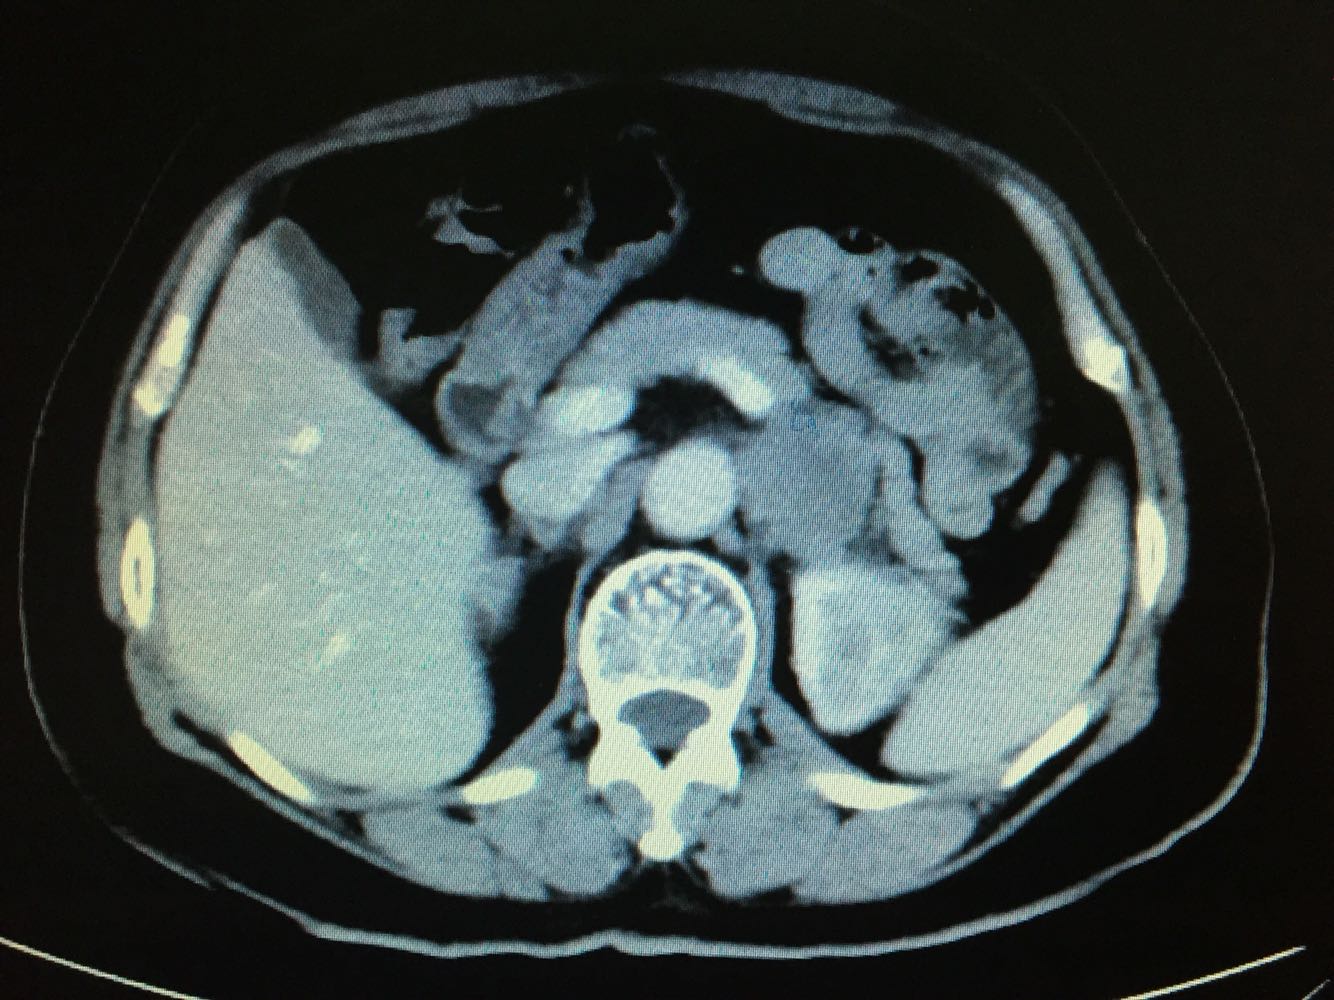

CT提示,左侧肾门处雪人样占位,包裹左肾静脉,左肾积水,与胰腺及左肾关系密切,血常规,肝肾功未见明显异常,GFR左侧27,右侧58。

诊断,左侧腹膜后占位:淋巴瘤?或者淋巴样增生?,侵犯周围器官组织?

探讨下一步治疗方案:该肿瘤位置位于肾门,无法穿刺活检,拟行腹腔镜下探查切除。但,肿瘤与周围组织器官关系密切,术中有可能左肾保不住。但,如果是淋巴瘤的话,化疗效果是很好的。术中快速冰冻,根据病例结果制定方案!